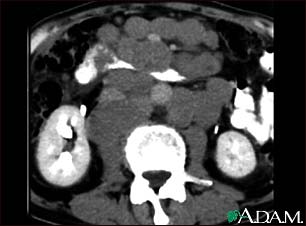

This abdominal CT scan shows tumor masses (malignant lymphomas) in the area behind the peritoneal cavity (retroperitoneal space).